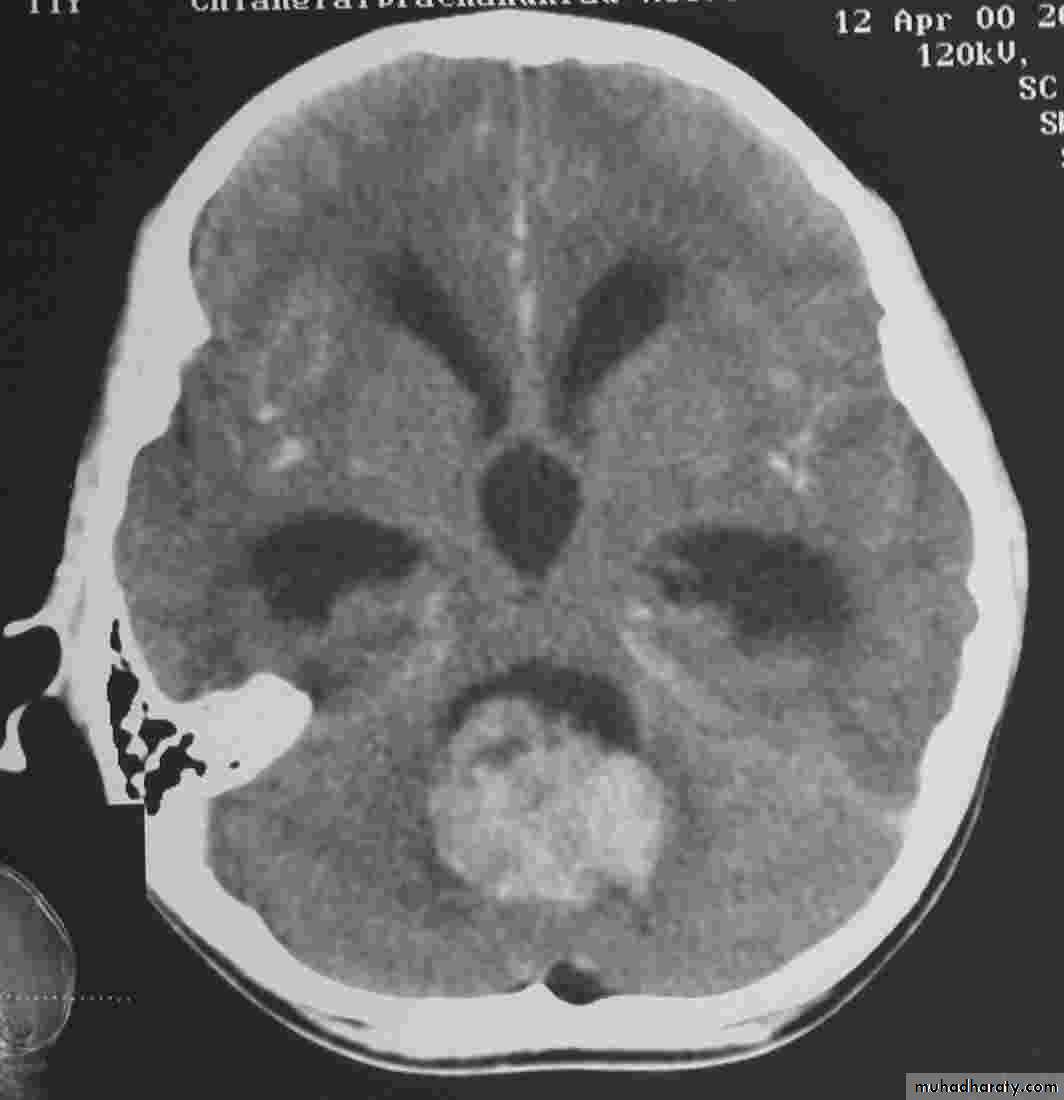

Meningioma

Benign tumor arise from the arachnid cells of the meningeal covering of the brain are most common primary intracranial neoplasm

Usually present in middle age female

it is well defined extra axial , located mainly at the convexity of the skull periphery

rounded or sessile , plaque like , specially the tumor arise from the cribriform plate , or those arise from the petrus bone , planum spheniodale , or from skeleton of the pituitary fosse .

CT finding

meningioma presented as isodense area or slightly hyper density area with surrounded crescent of hypo density ( csf cap ) post contrast injection the lesion enhance homogeneously with enhancing Dural tail .

20 % show calcification

hyperostosis & thickening of the near by bony part of the skull & diplioc space .

it may be associated with little or no peri focal edema .